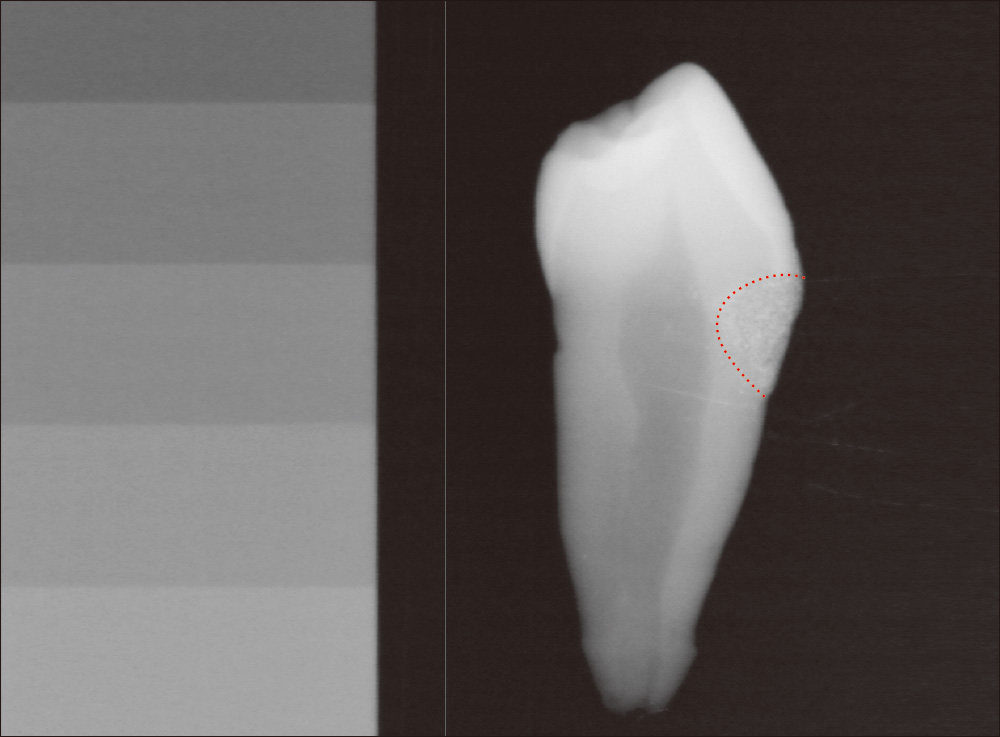

![[写真] X線画像](/academic/dentalmagazine/wp-content/uploads/sites/2/2026/04//196-6_photo06.jpg)

図6 色調適合性にも優れた造影性フィラーを配合。アルミニウム100%相当のX線造影性がある。(提供:サンメディカル株式会社)

⑤X線造影性の付与

これまでの「ボンドフィルSB」シリーズは、X線造影性がなかったため、充填後のレントゲン撮影では、内部気泡の有無や辺縁の適合状態、充填部位下での二次う蝕の有無などを正確に診断することが難しかったが、今回のリニューアルで新しく色調適合性にも優れた造影性フィラーを配合したことにより、それらの問題は克服された。

X線写真の撮影によって、経過観察できることは長期的な予後観察を容易にし、患者との信頼関係を維持することに寄与すると考えている。